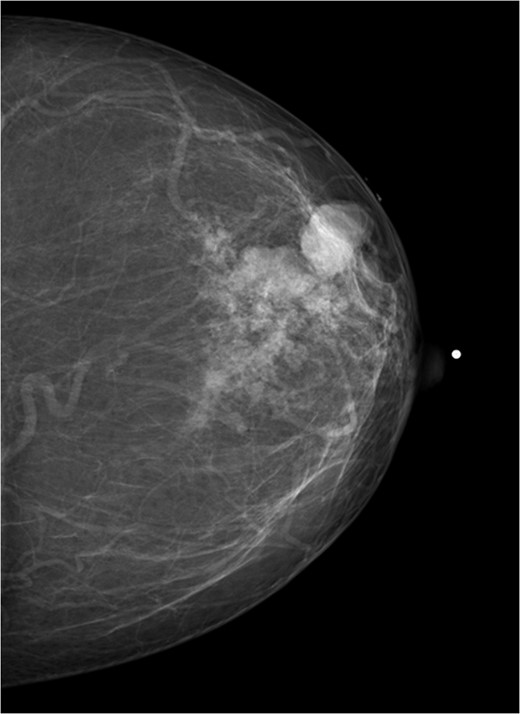

A 56-year-old black female presented to the surgical clinic with a palpable left breast mass that had grown over several months. She denied nipple discharge, breast retraction or family history of malignancy. Physical exam revealed a palpable, subareolar mass without skin changes or asymmetry, and no lymphadenopathy. Her mammogram revealed a 5.4 × 3 cm lesion behind the nipple with Breast Imaging-Reporting and Data System (BI-RADS) 5 classification. An ultrasound indicated a 2.2 × 2 cm lobulated hypoechoic mass with BI-RADS 4 classification (Figs 1–3).

Mammogram mediolateral view of left breast showing lesion posterior to nipple BI-RADS 5.

The patient was then sent for MRI of the breast to detail the extent of the remaining mass. This revealed an ill-defined mixed linear and fine nodular enhancing tumor 6.5 × 4.6 × 4.8 cm in size with BI-RADS 5 (Figs 4–7).